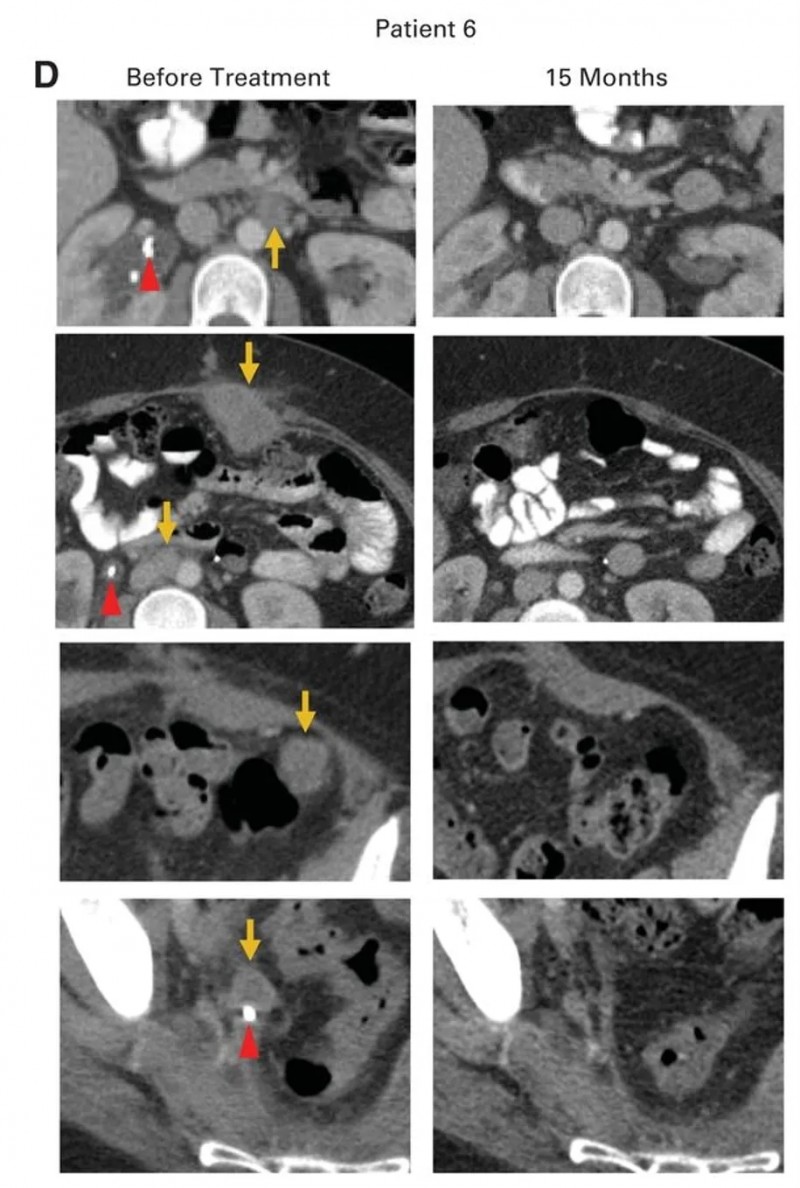

患者6是一位转移性腺癌,原发肿瘤对放化疗耐药,经挽救性手术后病情仍进展,转移病灶累及腹主动脉旁淋巴结、腹壁、主动脉腔静脉淋巴结、左侧结肠周围盆腔肿块和右侧输尿管结节等部位(详见下图D,金色箭头所示),还伴随右侧输尿管肾积水、双侧肺栓塞等并发症,需要放置输尿管支架和抗凝治疗。而在接受HPV-TIL治疗后,实现完全临床缓解(详见下图D),且治疗后15个月无复发迹象,右侧输尿管支架也在肿瘤消退后顺利取出。

▲图源“JCO”,版权归原作者所有,如无意中侵犯了知识产权,请联系我们删除